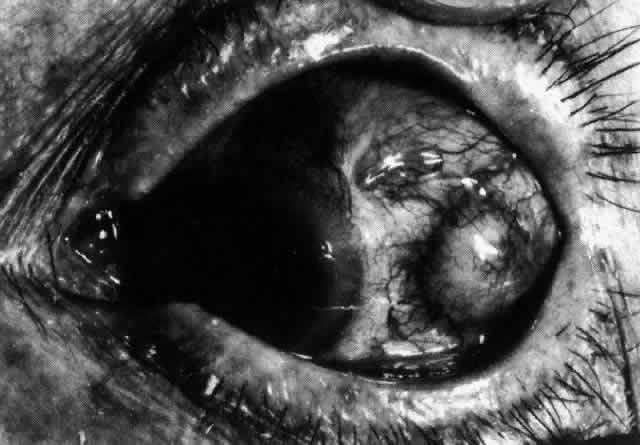

The sclera that is edematous is pushed forward, and the deep episcleral network is more congested than the superficial networks (Figs. 27 and 28). It is usually easy to ascertain by simple observation that the patient has scleritis and not episcleritis. However, it is not as easy to ascertain whether the patient has early necrotizing scleritis. It is in these patients that fluorescein angiography has considerable value, because the first changes are detectable in the ocular vasculature. Prompt and adequate treatment can prevent these changes from becoming irreversible.

Fig. 27. In scleritis, maximum congestion occurs in deep episcleral plexus, which is bowed forward by underlying scleral edema. Episcleral tissue is slightly infiltrated and superficial plexus is slightly congested (see Fig. 14). (Watson PG, Hayreh S, Awdry P: Episcleritis and scleritis. Br J Ophthalmol 52:278–279, 1968)

Fig. 28. Nodular scleritis. Both the anterior conjunctival slit and the deep scleral slit are displaced forward by the scleral edema. There is little separation between these two beams, indicating that all the edema is in the sclera and not in the overlying episclera. (Watson PG, Hayreh S, Awdry P: Episcleritis and scleritis. Br J Ophthalmol 52:278–279, 1968)